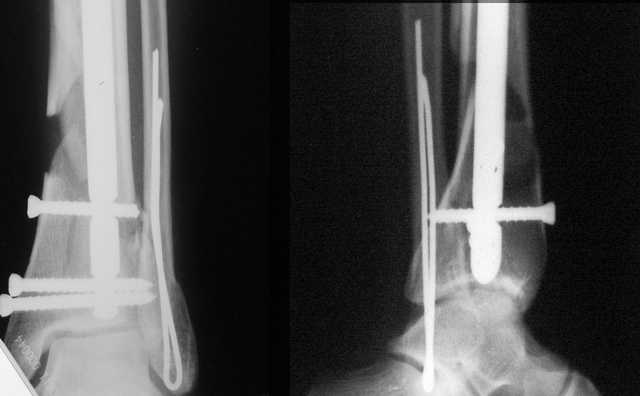

В приложении остеосинтез перелома шейки плеча LPHP у доктора из нашей клинике , через 8недель уже трудился в операционной

Кликните для загрузки файла 06.JPG

20KB (21241 bytes)

АМ> В приложении остеосинтез перелома шейки плеча LPHP у доктора из нашей

АМ> клинике, через 8недель уже трудился в операционной